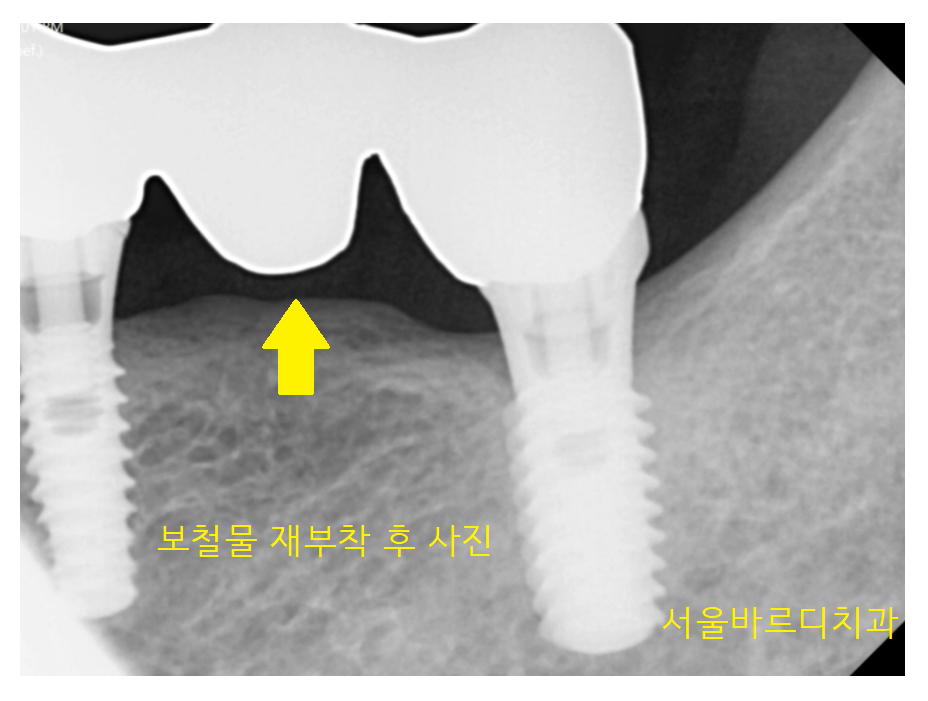

왼쪽 위에 부분을 자세히 보는 x-ray를 촬영해 보았습니다.

23.06.15

임플란트 사이와 사이에 공간이 생겨

음식물이 끼고

잇몸이 부었습니다.

마취 후 염증을 제거하는 치료를

진행하고

잇몸 연고를 주입하는 것으로 마무리해 드렸습니다.

23.07.11

x-ray로 보면 이렇게 생겼습니다.

남은 임플란트 1개는 상태가 괜찮아

그대로 쓰시기로 하고

임플란트가 빠진 곳에 치료 계획을 다시 잡아드렸습니다.